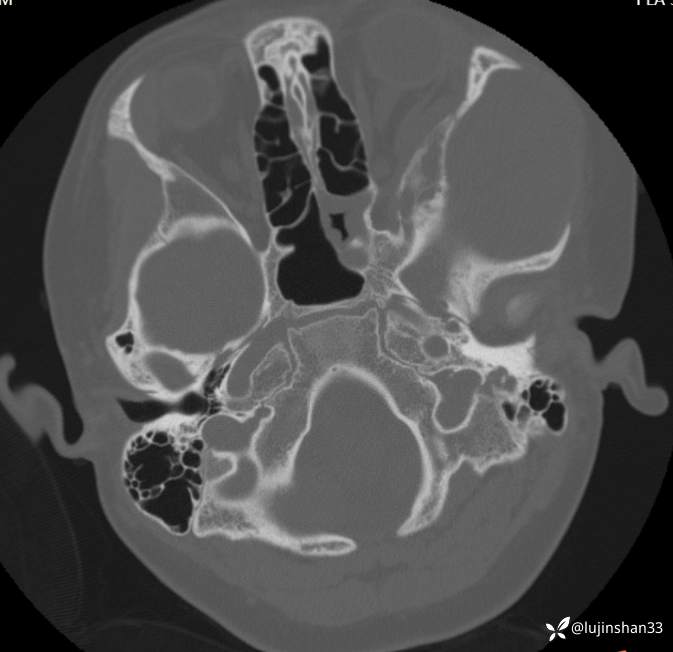

颞骨CT:2020年12月